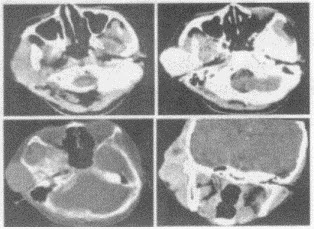

女,19岁,右侧面颊部肿胀1年,CT检查如图所示,最可能的诊断是()